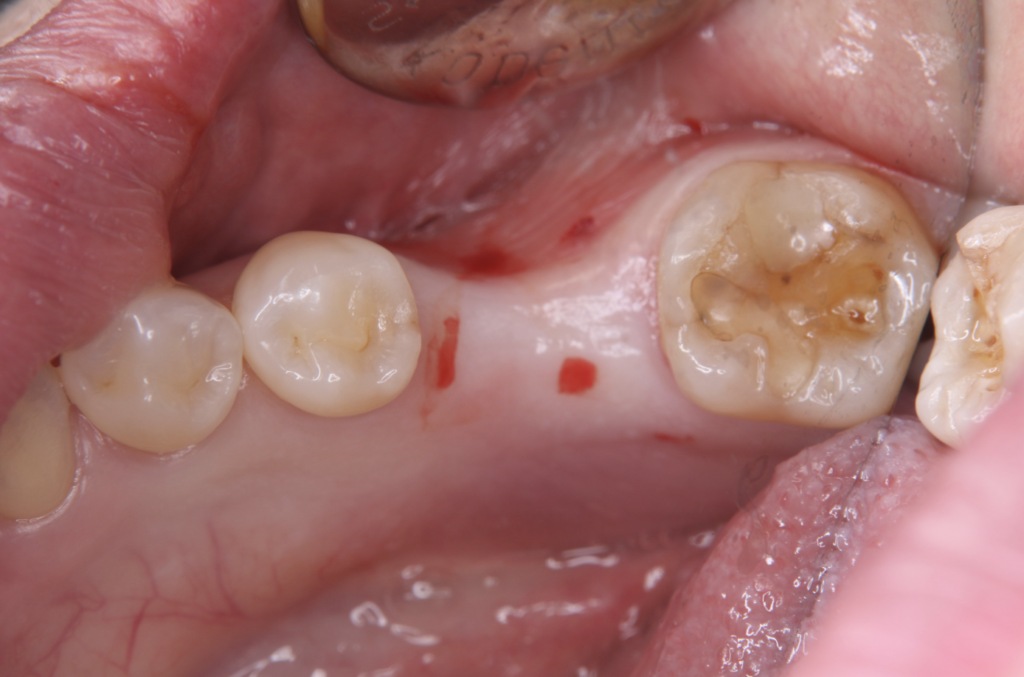

今回のケースでは、

欠損部の奥にある親知らずが

・大きさ

・歯根の形態

ともに適しており、移植可能と判断しました。